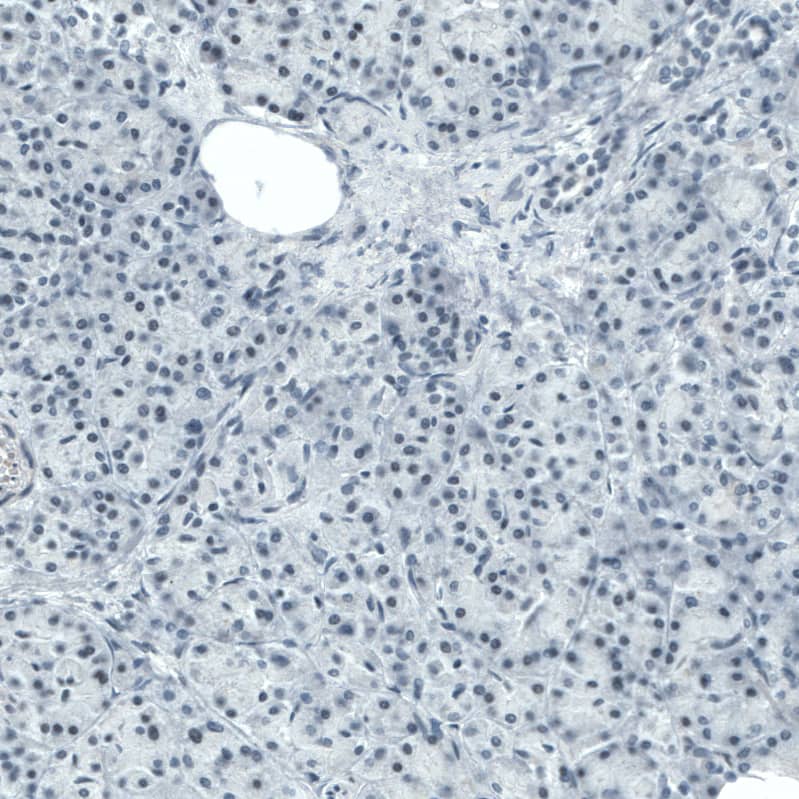

Staining of human pancreas shows no positivity in exocrine glandular cells as expected.